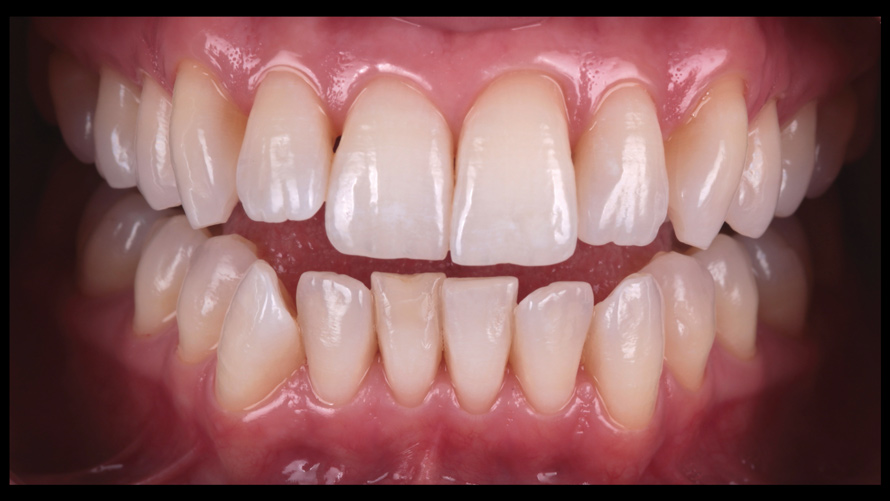

(8.) Routine case photograph taken with a smartphone and an EALS device.

Figure 8

(9.) Preoperative esthetic case documentation using a smartphone and an EALS device.

Figure 9

(10.) Preoperative esthetic case documentation using a smartphone and an EALS device.

Figure 10

(11.) Preoperative esthetic case documentation using a smartphone and an EALS device.

Figure 11